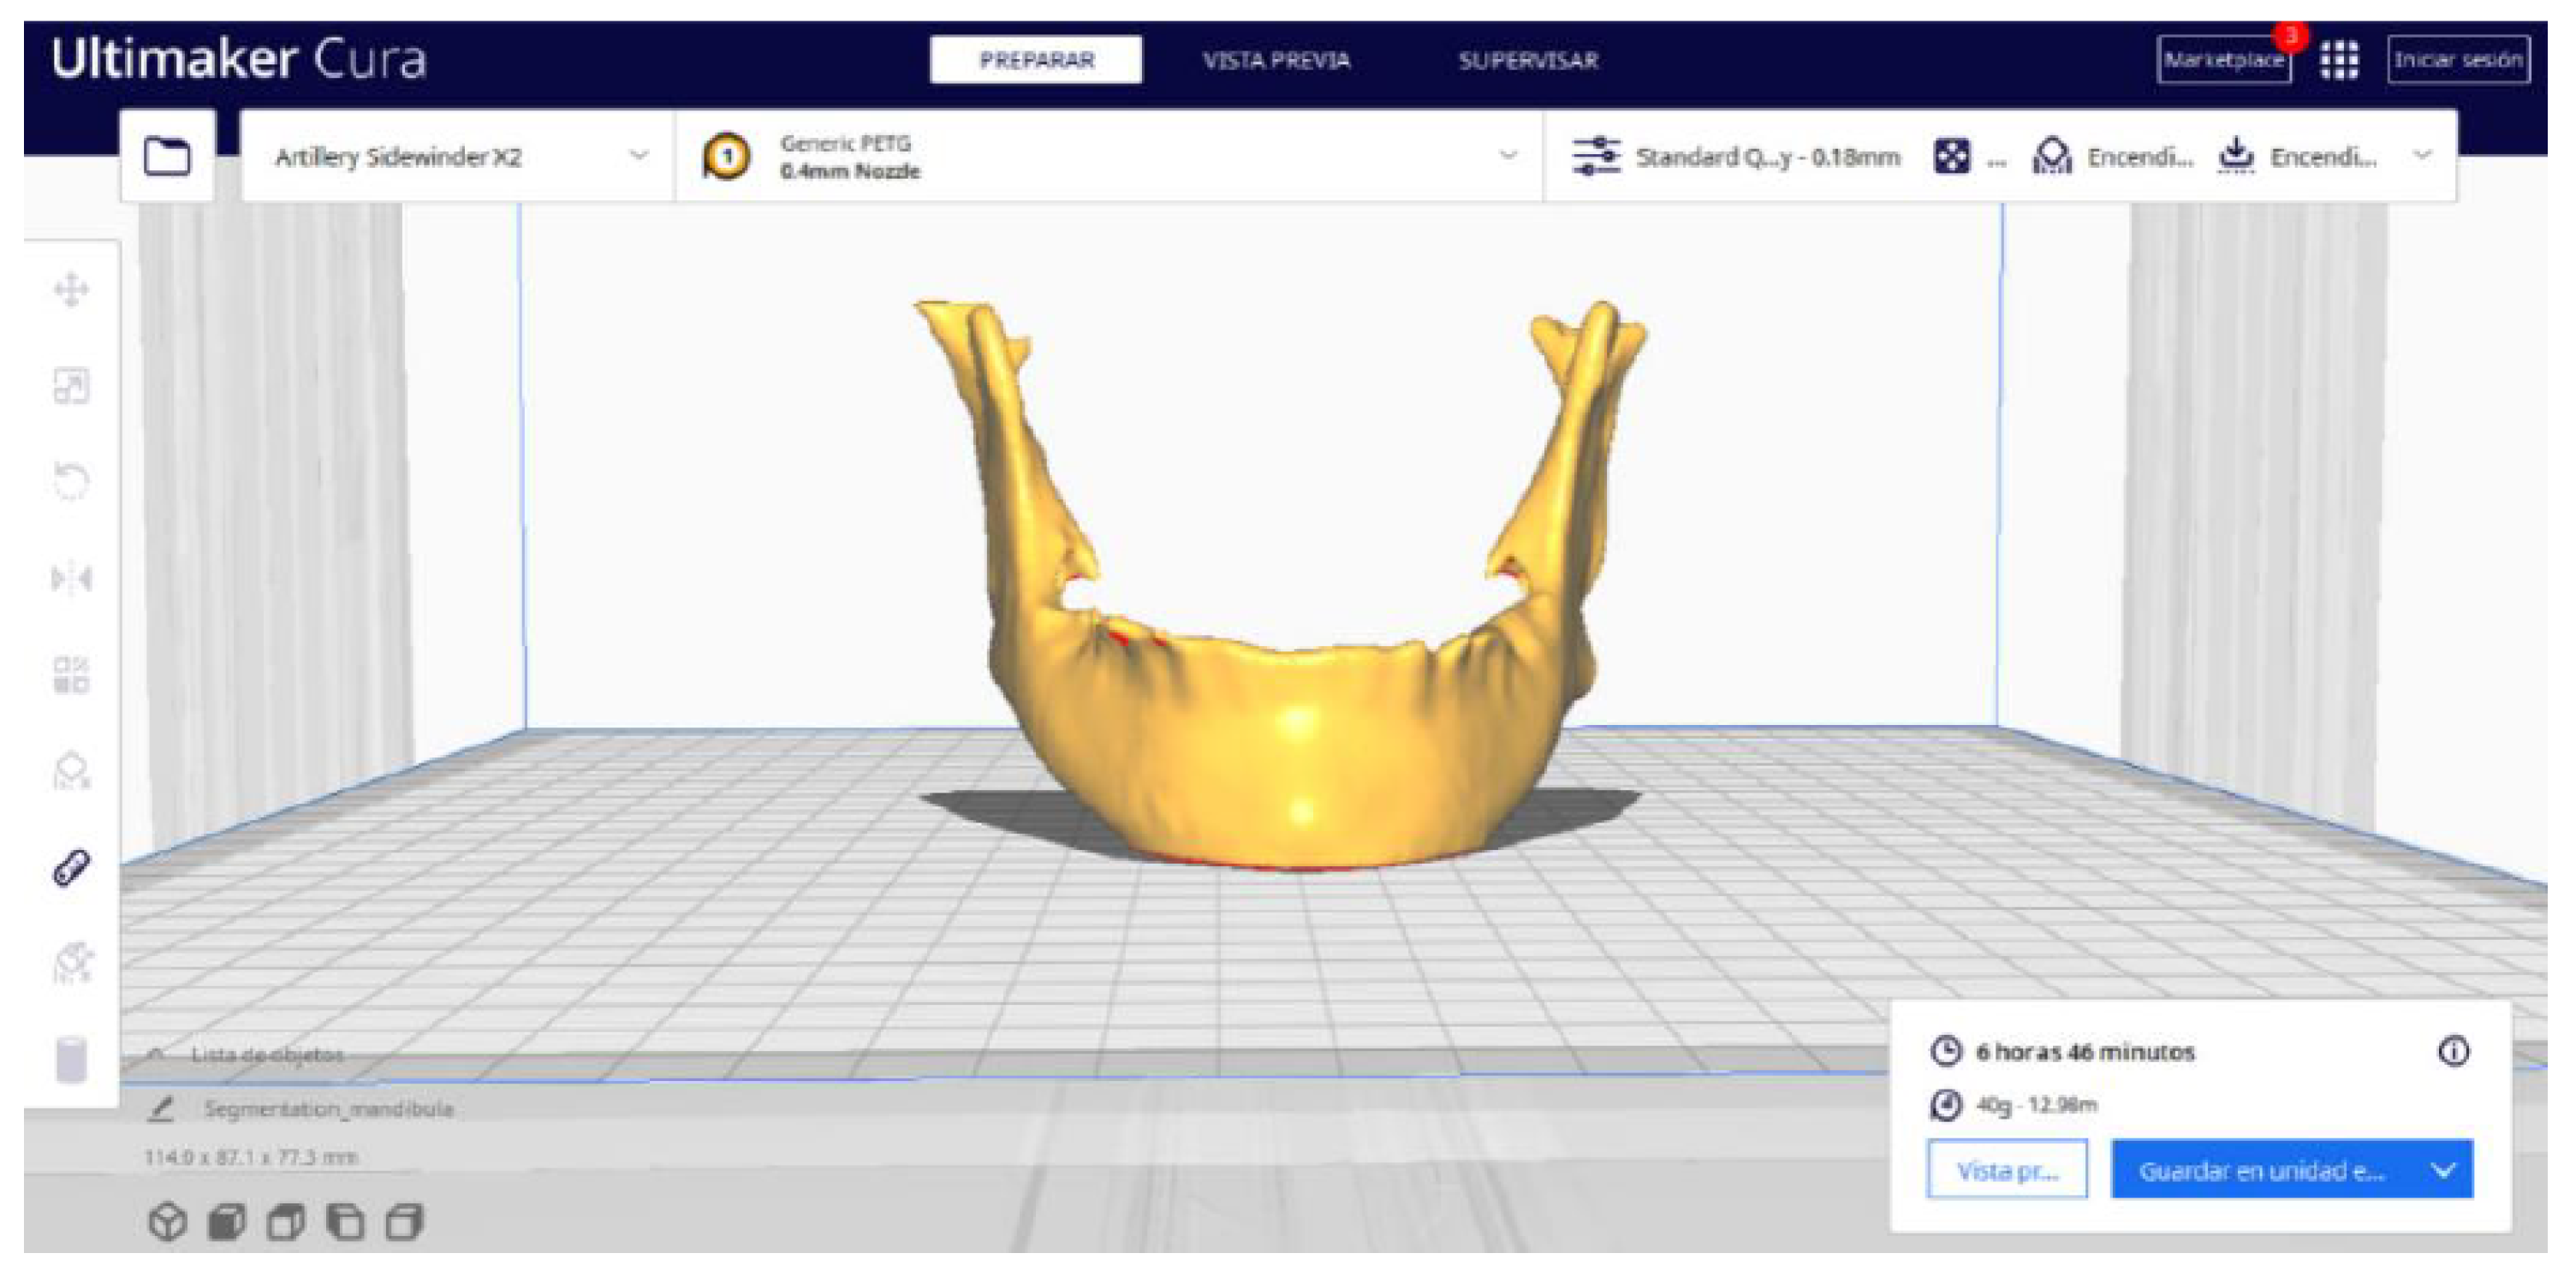

3.2.2. STL-to-GCODE Files

2.2. STL-to-GCODE File Conversion

- Launch the Ultimaker Cura program on your computer.

- Open the STL file you want to print from the “Open File” option in the menu.

- Access the printer settings within Ultimaker Cura.

- Be sure to select the appropriate printer model and material settings for your 3D printer.

- If necessary, make adjustments to the position, scale, or rotation of the model on the build platform within Ultimaker Cura. This allows you to optimise the layout of the model on the printing platform.

- Adjust the layer height and line width to refine the print quality, considering the balance between print resolution and time efficiency.

- Choose the appropriate support structure type and pattern to ensure the successful printing of complex geometries, adjusting the adhesion to the build plate as necessary.

- In order to continue the STL file to GCODE conversion process, select the “Segmentation” option in Ultimaker Cura.

- The segmentation tool provides valuable information such as the estimated model weight and estimated printing time, among other crucial data.

- Once the segmentation is complete, go to the “Preview” option. Here, a sidebar will appear on the right side of the screen, giving you the ability to preview the materialisation process layer by layer, from the base to the top of the model.